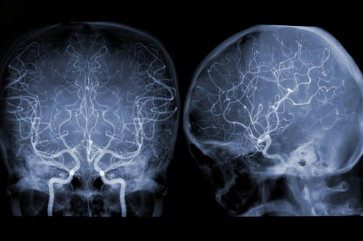

안녕하세요, 여러분! 혹시 모야모야병이라고 들어보신 적 있으세요? 이는 뇌동맥 조영 영상이 아지랑이처럼 흐물흐물해지면서 뿌연 담배 연기 모양과 비슷하다고 하여 "모야모야"라고 명명되었다고 하는데요. 이름이 참 재미있는 것 같습니다. 허나, 이 병은 아직 정확한 원인이 밝혀지지 않았으며, 주로 아이들에게 많이 발병하는 무서운 병 중 하나라고 합니다. 오늘은 모야모야병에 대한 증상, 원인, 진단 그리고 치료 및 예방법까지 자세히 알아보는 시간을 가져보도록 하겠습니다.

뇌혈관의 구조를 확인하기 위해 영상 검사가 주로 사용됩니다. 이러한 검사에는 자기 공명영상 촬영(MRI), 컴퓨터 단층 촬영(CT), 혈관조영술(angiography)이 포함될 수 있습니다. MRI 및 CT는 뇌혈관의 형태와 혈류를 시각화하는 데 사용됩니다. 혈관조영술은 혈관 내부에 감압제를 삽입하여 혈관의 형태와 혈류를 더 자세히 확인합니다.